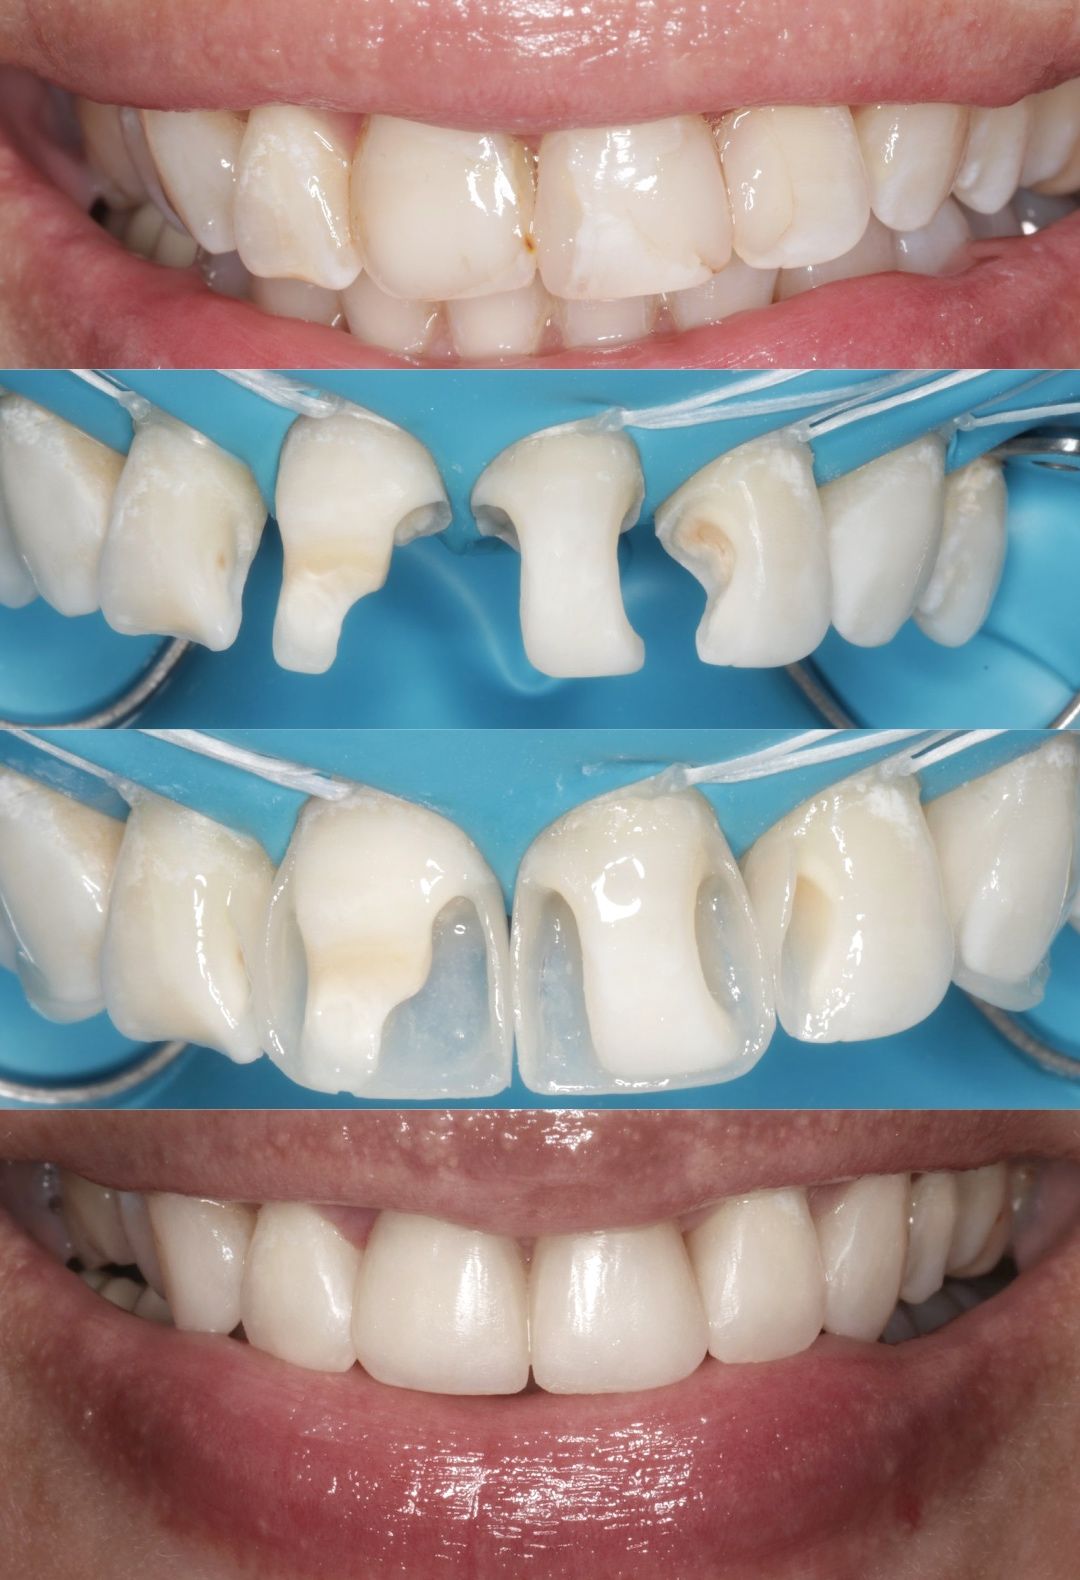

Jej pasją jest leczenie zachowawcze, wypełnienia z jej ręki są małymi dziełami sztuki, idealnie i anatomicznie wykończonymi. Precyzja i cierpliwość w sposobie pracy w połączeniu z wysokim poczuciem estetyki umożliwiły tej naturalny rozwój w kierunku stomatologii estetycznej. Dr Valeriia wykonuje precyzyjne kompozytowe odbudowy zębów przednich, bondingi oraz prace „z ręki”.

Doktor uważa, że obraz mówi więcej niż słowa, zapraszamy do zapoznania się z galerią jej prac.